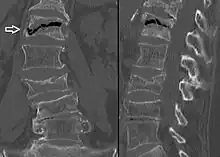

A compression fracture is a collapse of a vertebra. It may be due to trauma or due to a weakening of the vertebra (compare with burst fracture). This weakening is seen in patients with osteoporosis or osteogenesis imperfecta, lytic lesions from metastatic or primary tumors,[1] or infection.[2] In healthy patients, it is most often seen in individuals suffering extreme vertical shocks, such as ejecting from an ejection seat. Seen in lateral views in plain x-ray films, compression fractures of the spine characteristically appear as wedge deformities, with greater loss of height anteriorly than posteriorly and intact pedicles in the anteroposterior view.[3]

Compression fractures are usually diagnosed on spinal radiographs, where a wedge-shaped vertebra may be visible or there may be loss of height of the vertebra. In addition, bone density measurement may be performed to evaluate for osteoporosis. When a tumor is suspected as the underlying cause, or the fracture was caused by severe trauma, CT or MRI scans may be performed.

Compression fracture of the fourth lumbar vertebra post falling from a height.